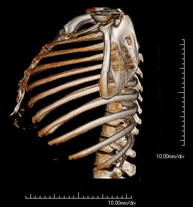

- TC Tórax

Prueba diagnóstica que consiste en obtener imágenes del tórax de alta definición anatómica (pulmones, corazón, mediastino, grandes vasos, caja torácica, etc.) mediante el empleo de un equipo de TC (Tomografía Computarizada). Dichas imágenes se estudian posteriormente en una estación de trabajo que permite reconstrucciones bidimendionales en diferentes planos del espacio y también reconstrucciones 3D (volumétricas). Algunos estudios requieren el empleo de contraste yodado para mejorar la definición de las imágenes. - Angio-TC Aorta torácica

Exploració radiològica que mitjançant un sistema de raigs X i detectors que giren al voltant del pacient i que reconstrueixen les imatges per ordinador, permet l'estudi detallat de l'estern. - TC Clavícules

Exploració radiològica que mitjançant un sistema de raigs X i detectors que giren al voltant del pacient i que reconstrueixen les imatges per ordinador, permet l'estudi detallat de les clavícules. - TC Parrilla costal

Exploració radiològica que mitjançant un sistema de raigs X i detectors que giren al voltant del pacient i que reconstrueixen les imatges per ordinador, permet l'estudi detallat detalla de la Parrilla. - Angio- TC Cardíac o TC Cardíac